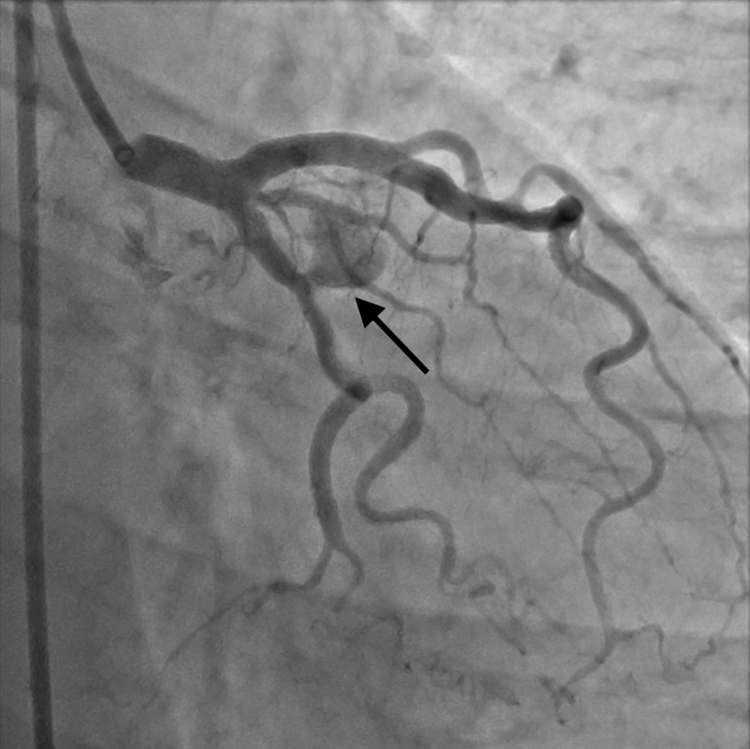

| Túi giả phình động mạch trước can thiệp - Ảnh BVCC |

Kết quả cho thấy bệnh nhân bị hẹp 30% nhánh chéo D1 và có túi giả phình động mạch vành với kích thước 7.6 x 11.6 mm không huyết khối tại đoạn gần nhánh động mạch mũ.

Theo ThS. BS. Trần Tấn Việt, Trưởng Khoa Can Thiệp Tim Mạch Bệnh viện đa khoa Xuyên Á, tình trạng có giả phình động mạch vành ở người bệnh rất dễ dẫn đến vỡ giả phình và gây tràn máu màng ngoài tim, có thể dẫn đến tử vong nhanh chóng.